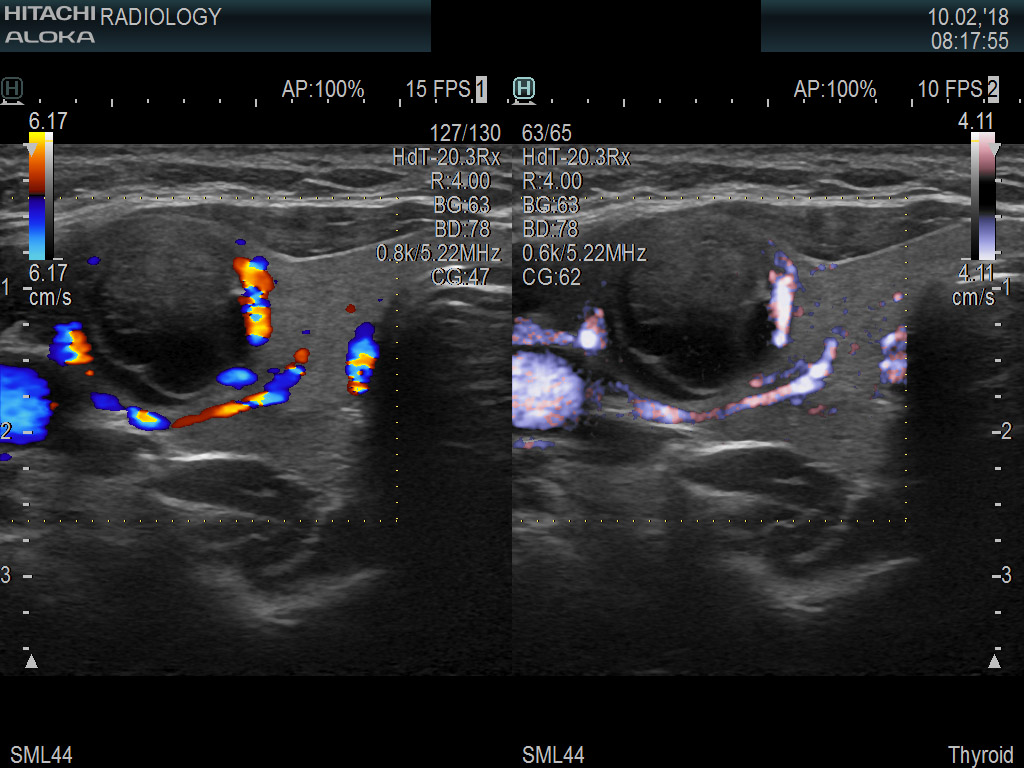

Superior guidance for all applications

Fujifilm Healthcare Americas is committed to designing tools that help surgeons navigate inside the human body and provide the necessary information to immediately make critical surgical decisions.

Fujifilm Healthcare's dedication to Surgeons provides outstanding ultrasound technology, professional support and the specialized tools necessary to best perform comprehensive real-time ultrasound imaging in Breast Surgery, General Surgery, Laparoscopic Surgery, Neurosurgery, Robotic Surgery and Surgical Oncology.

Imaging Clearly Defined

State-of-the-art digital architecture and advanced imaging features to redefine the capabilities of surgical ultrasound.